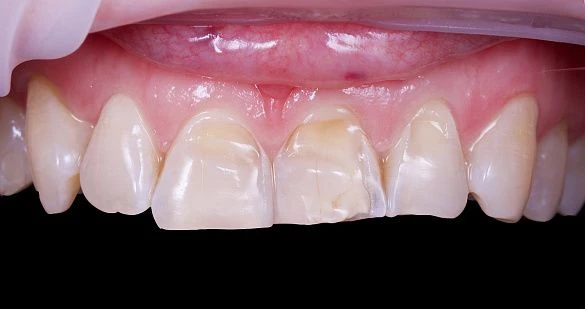

Наши работы